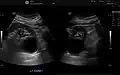

The complex cyst can be further evaluated with doppler ultrasonography, and for Bosniak classification and follow-up of complex cysts, either contrast-enhanced ultrasound (CEUS) or contrast CT is used.[13]

Renal ultrasonography of a simple renal cyst with posterior enhancement. -

Renal cyst as seen on abdominal ultrasound -